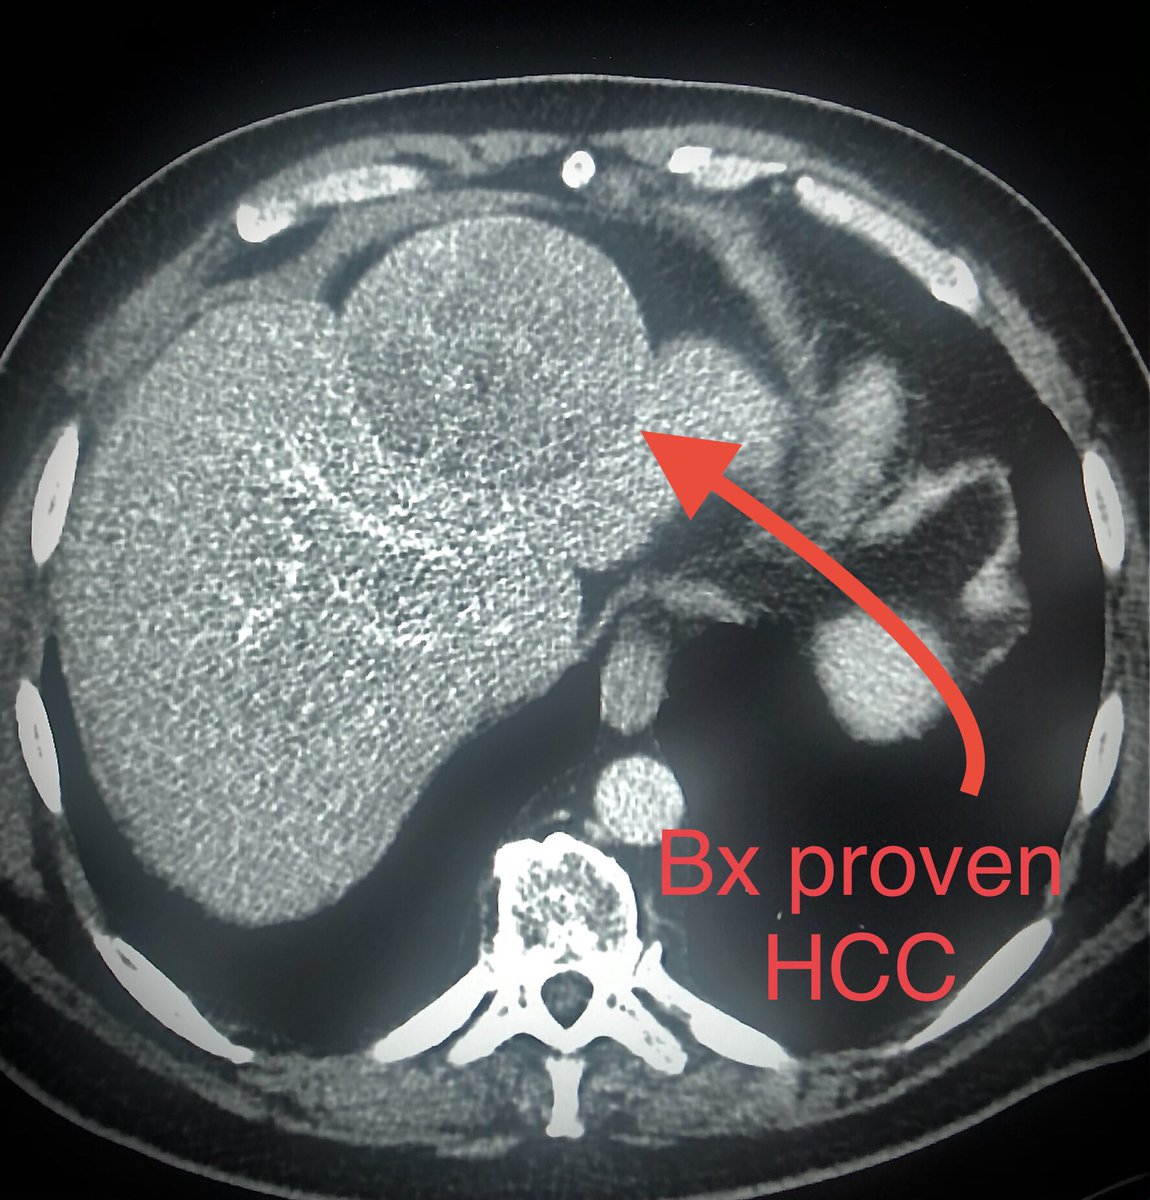

Very satisfying to remove these when appropriate in conjunction with other minimally invasive approaches #venaseal #Ablation #sclerotherapy